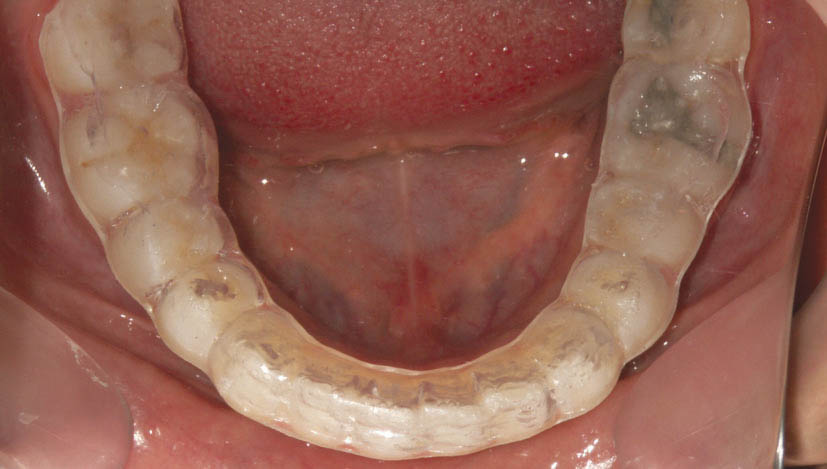

برای خارج کردن لترال از کراس بایت، به بایت پلیت خلفی نیازمندیم. اگر ارتودنسی فقط برای فک بالا انجام شده است برای فک پایین اسپلینت آکریلی میگذاریم (شکل 191-1) و اگر هر دو فک را ارتودنسی کردهاید مقداری کامپوزیت روی سطح اکلوزال دندانهای خلفی بگذارید تا بایت باز شود (شکل 192-1).

شکل 191-1: اسپلینت آکریلی روی فک پایین